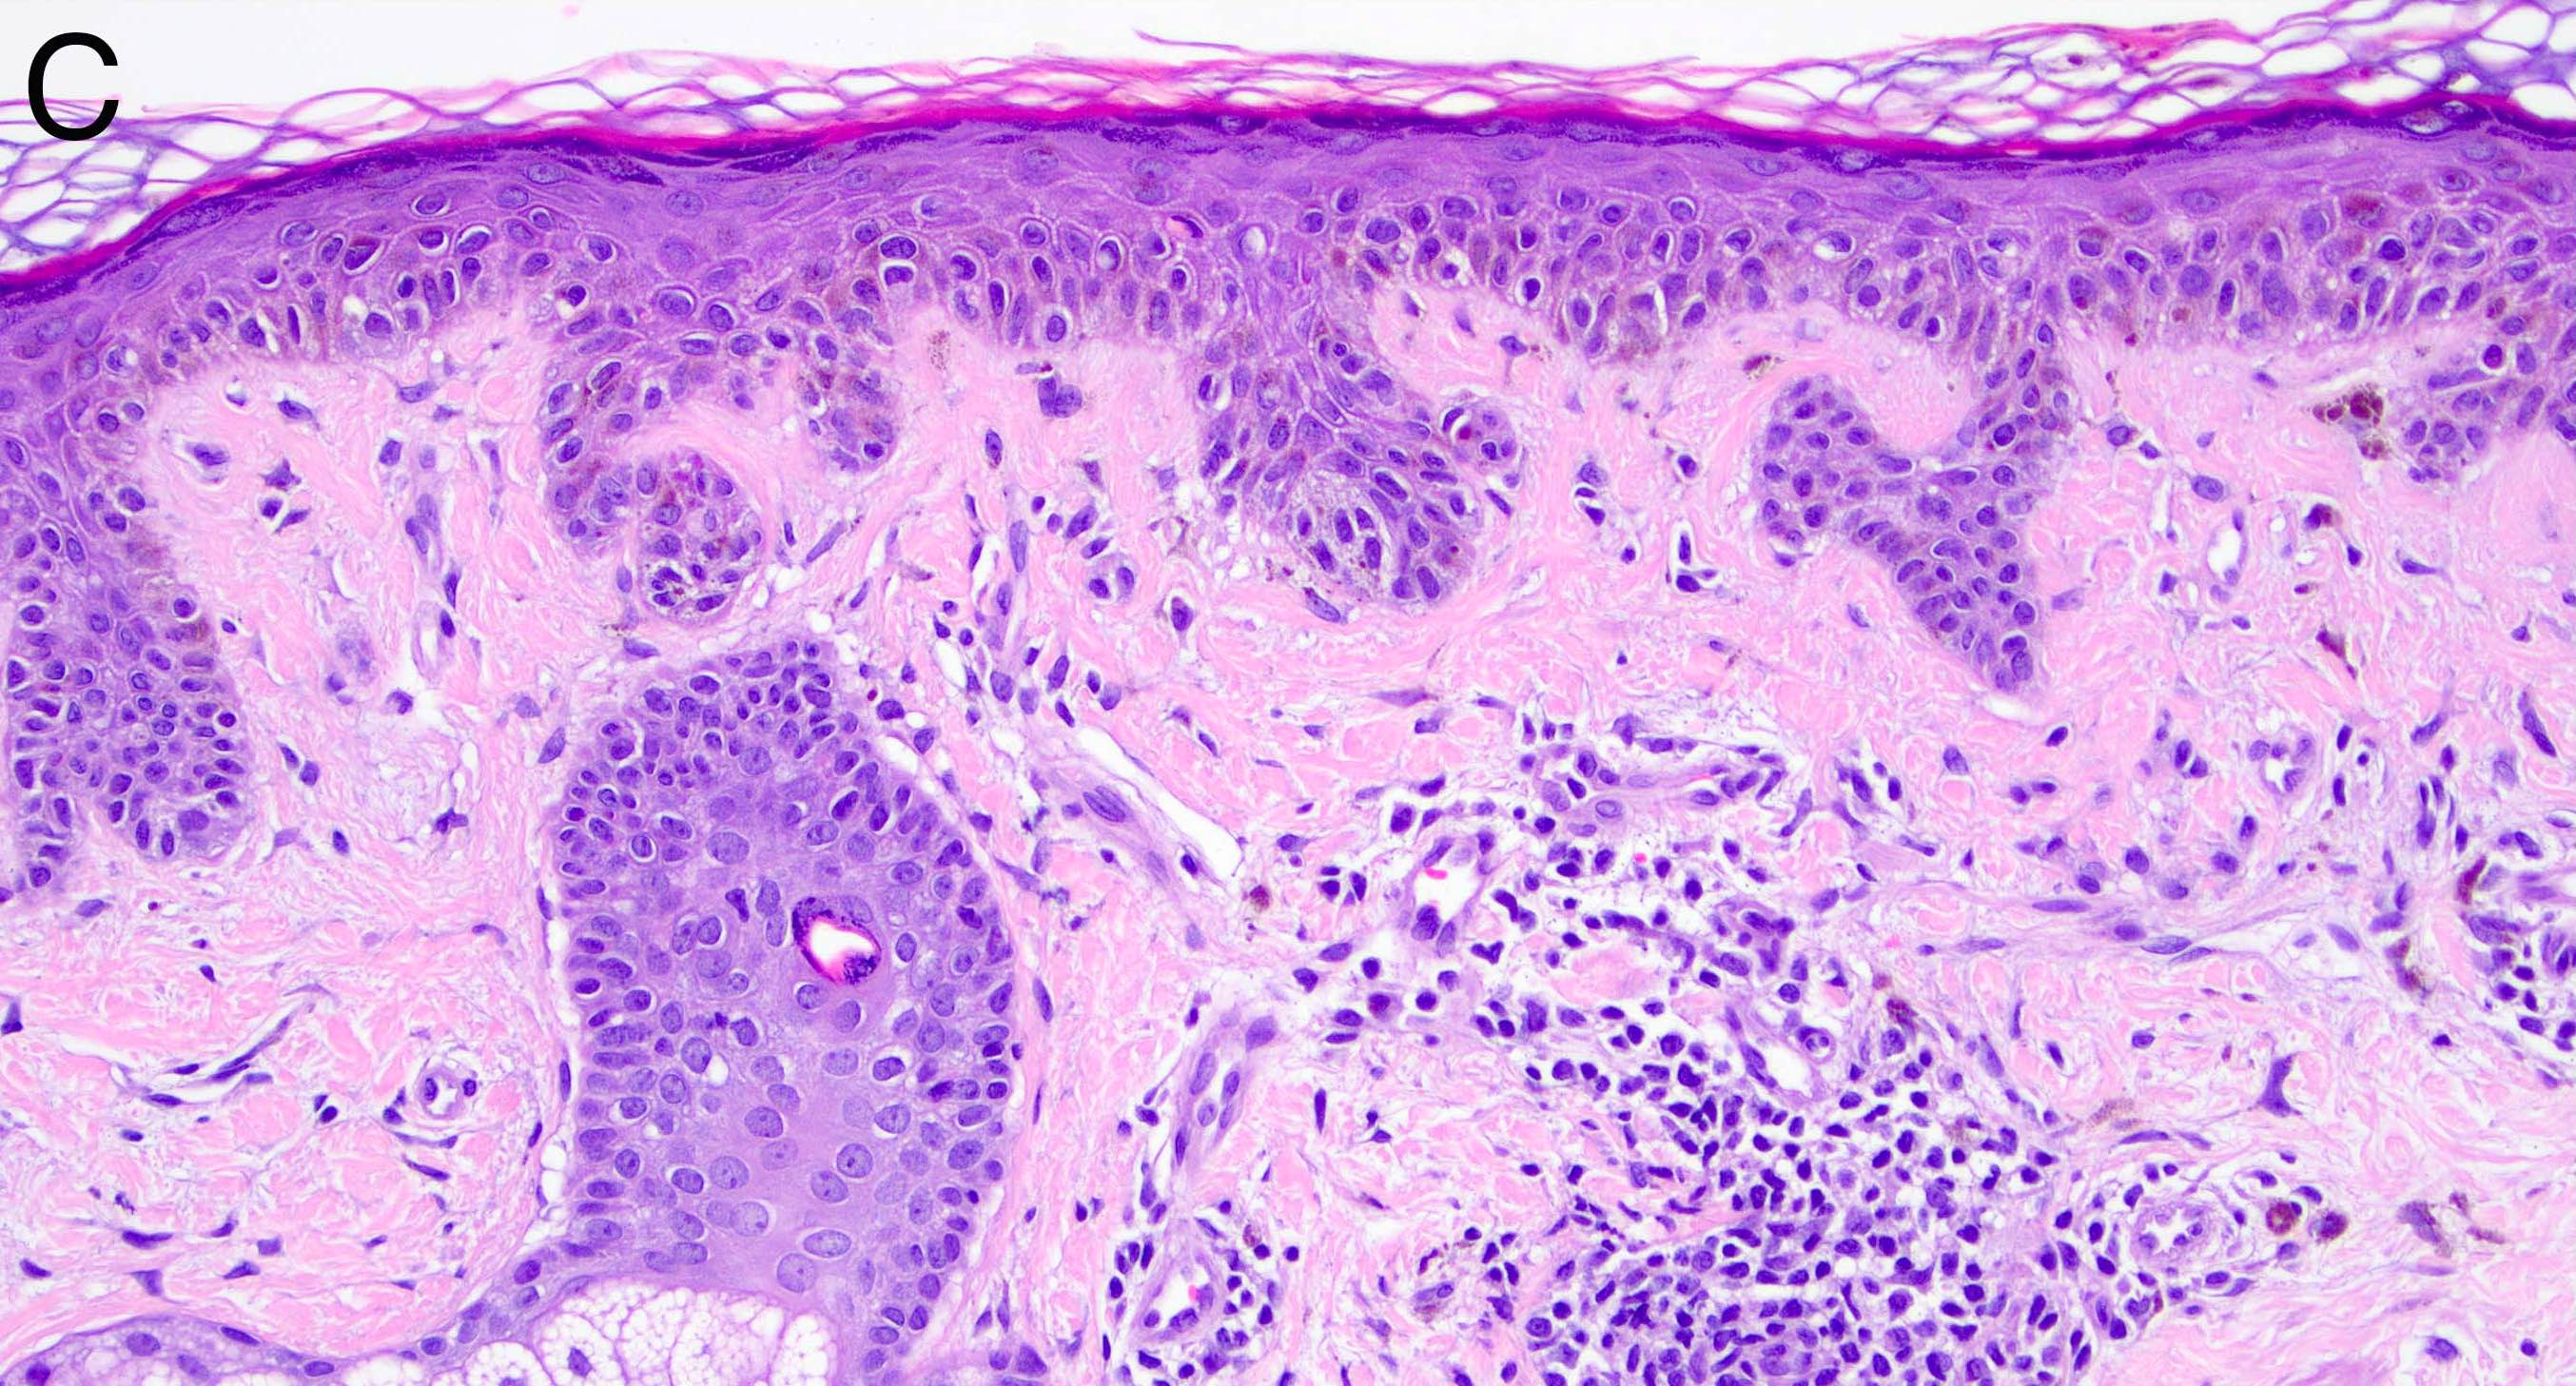

- Melanocytic nevi of the genitals (Am J Surg Pathol 2008;32:51):

- May contain large dyshesive irregular nests in close proximity to one another

- May contain a prominent lentiginous component

- Deeper nests may evoke a stromal fibrotic host response

- Lesion should maintain symmetry, circumscription and maturation

- Pagetoid growth can be seen but typically does not extend into granular layer

- Junctional component may extend into adnexal structures

- Significant cytologic atypia can occur